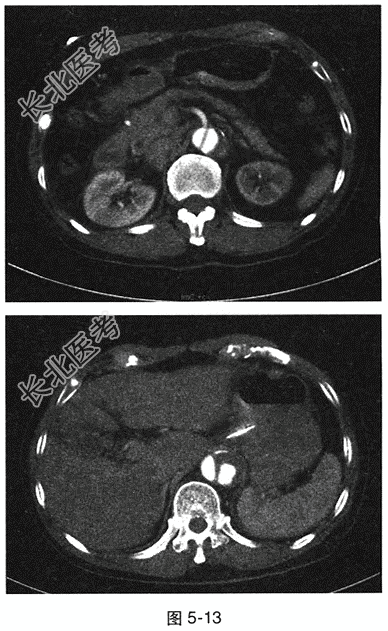

- 多项选择题2.[提示]ECG:窦性心律, HR38次/min,Ⅱ、Ⅲ、aVF导联ST段压低0.1mV。实验室检查: 外周血WBC 13.7×10⁹/L,N 0.873; ALT 180U/L,AST 146U/L, 白蛋白28.0g/L,血淀粉酶165U/L, 脂肪酶1117.0U/L。腹部增强CT见图5-13。患者可能的临床诊断为

- 多项选择题3.[提示]腹部CT显示:主动脉内散在低密度血栓影, 可见内膜钙化内移,初始破口位于升主动脉, 范围累及胸主动脉至腹主动脉分叉处。 此患者的类型为